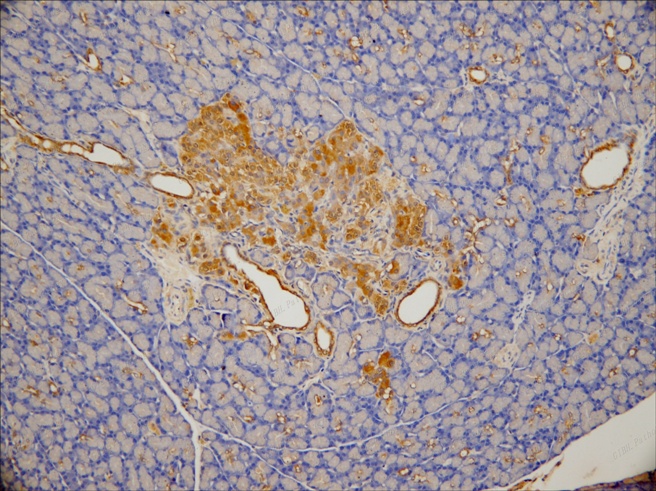

給藥4 組化 20x